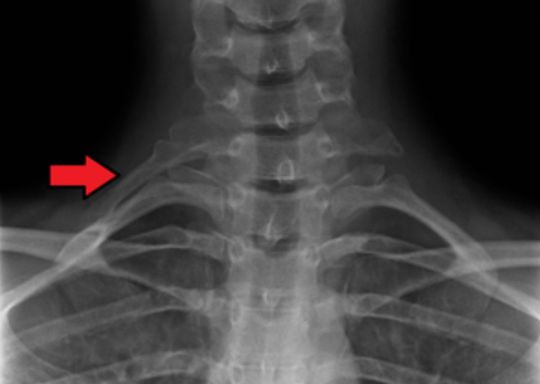

Diagnosis?

Right side c7 cervical rib

Cervical rib